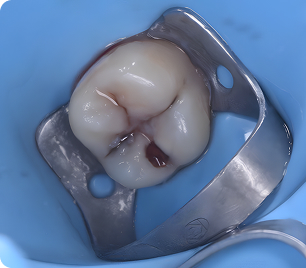

Специализация: лечение кариеса, пульпита и периодонтита временных зубов